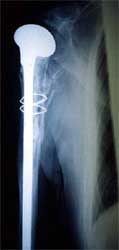

肱骨干纵行劈裂的大骨片不要轻易摘除,应用钢丝捆绑

或者用0.8mm钢丝穿过肱骨大结节,固定到肱骨近端